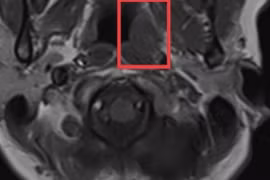

Bé trai đau đầu hơn nửa tháng, uống thuốc không đỡ khiến người thân lo lắng, đưa đi khám. Tại bệnh viện, bác sĩ thông báo nguyên nhân khiến gia đình ngã quỵ vì không tin vào tai mình.